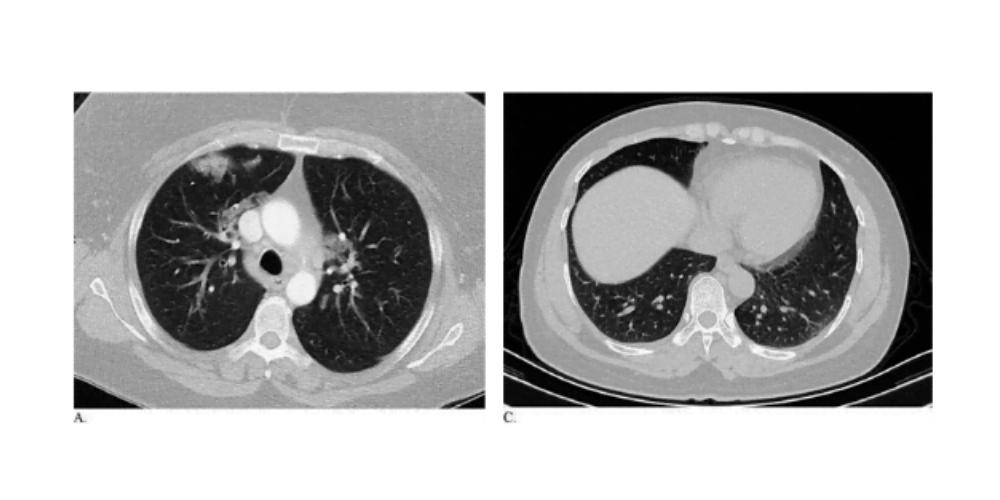

Furthermore, the investigators also noted multiple CT patterns that were found to be much more common in patients with coronavirus disease 2019 than in those without it. These patterns were ground-glass opacity, peripheral distribution, vascular thickening, fine reticular opacity, and reverse halo sign.